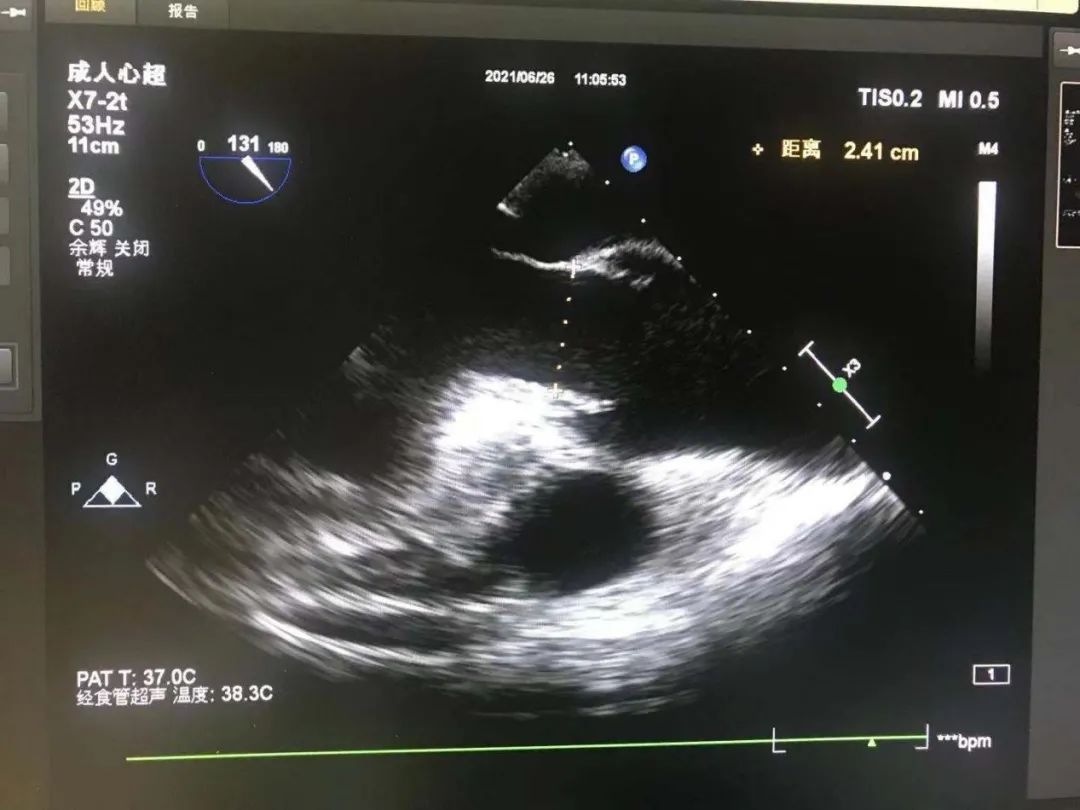

心脏彩超

食道超声再次测量瓣环径